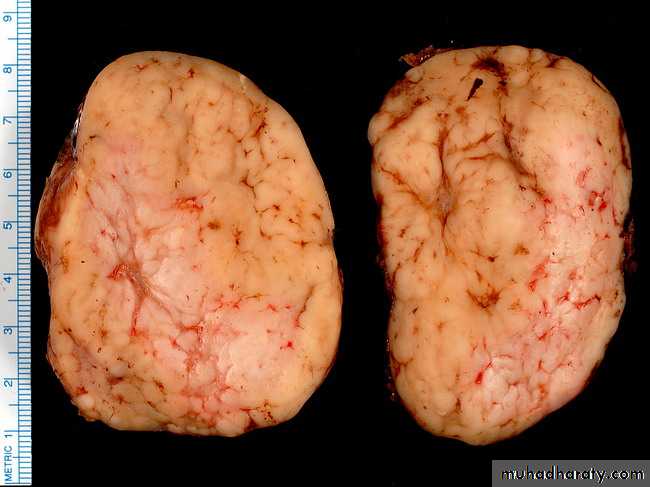

Gross features

lymph nodes involved by Hodgkin's lymphoma are enlarged, sometimes massivelyso. The gross appearance depend on the microscopic subtypes The consistency

varies from soft to hard depending on the amount of fibrosis

. Some degree of nodularity is often appreciated, particularly in the nodular sclerosis

Foci of necrosis may be present the cut surface of the node has a more heterogeneous

appearance than most non-Hodgkin's lymphoma. in advanced cases, several nodes from the same group

become matted together